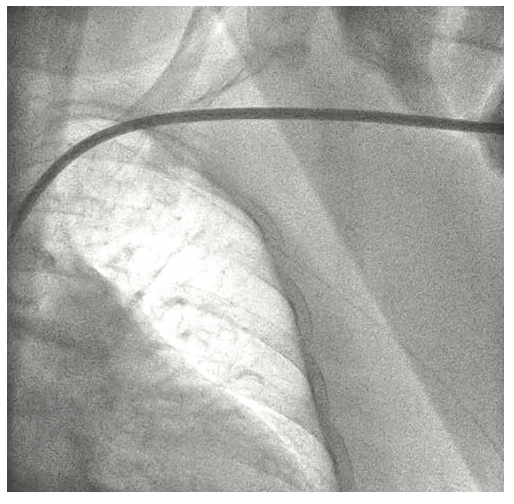

The right groin was accessed using fluoroscopic guidance. A micropuncture sheath was placed and upsized to a 7 French, 45 cm Destination sheath (Terumo) in the right groin. We accessed the right radial, but could not get good flow. Therefore, we ended up using the ulnar artery with ultrasound guidance and placed a Terumo 5/6 Slender sheath in the ulnar artery. We proceeded to access the left axillary artery. We placed a Judkins right (JR)4 catheter in the left subclavian and did a selective angiogram, documenting the location of the thoracoacromial artery and circumflex humeral (Figure 4); then using a Chiba biopsy needle (Cook), accessed the axillary artery and placed a 5-French 30 cm sheath (Cook)(Figure 5). We used the 15 cm biopsy needle to allow us a shallow angle of approach with the patient’s body habitus and to avoid “kinking” the sheath. We then switched out for the Lunderquist wire (Cook Medical), placed an 8 Fr sheath, and performed a pre-close using two Perclose devices (Abbott Vascular) (Figure 6).

Following the Perclose placement, we upsized to a 14 Fr x 13 cm Cook Medical sheath (Figures 7-8), and through that, advanced a JR catheter into the ventricle and switched out for the Impella 2.5 device (Figure 9). A JR4 and eventually, an Amplatz right (AR) mod, was used from the right ulnar to engage the RCA, and an Extra Backup (EBU) 3.5, 7 Fr (Medtronic) was used from the groin. Dual angiography was performed (Figure 10). Once the activated clotting time (ACT) was >300 seconds, the ramus was wired with a Marvel wire (Boston Scientific). We attempted to cross the LAD CTO using a Corsair (Asahi Intecc) and a Pilot 200 (Abbott Vascular). The Pilot 200 crossed, but it appeared to be in the diagonal and could not be redirected down the LAD. A Gaia second (Asahi Intecc) was able to cross into the LAD (Figure 11), and at that point, was switched out via the Corsair for a workhorse wire, a Runthrough (Terumo). An 0.9 laser (Spectranetics) was used perform laser atherectomy for a minute and a half on the LAD (Figure 12), but we could not get the catheter across. However, this allowed us to advance a balloon across the lesion and we predilated with a 1.5 mm x 20 mm Mini Trek (Abbott Vascular) and then a 2.0 mm x 20 mm balloon. The same 2.0 mm x 20 mm balloon was used in the ramus. A 2.5 mm x 15 mm AngioSculpt (Philips) was used to predilate the LAD, but on its return, the AngioSculpt became stuck and would not come back. We got it partially into the guide and then the shaft broke. We had part of the catheter in the guide and part of it in the coronary (the left main). We initiated a series of procedures to remove the AngioSculpt, first attempting use of a GuideLiner (Vascular Solutions) to envelope the balloon, but this was unsuccessful (Figure 13). The GuideLiner kept pushing the device further out. We tried trapping it; that was also unsuccessful. We were able to get a Mini Trek balloon distal, thinking it could be inflated and pulled back; that did not work. We then put the 4 wires down, wrapped the wires around and pulled back, getting it partially in the guide, but we could not get it all the way in. We got a Mini Trek down, used the GuideLiner to put a 2.0 down, and attempted an anchor technique that did not work, but this time, when we pulled the Mini Trek 2.0 back, it dislodged the balloon. The AngioSculpt was able to come in the guide and was removed without losing wire position. We rewired the ramus, performed dilation of the LAD and ramus with a 2.5 mm noncompliant balloon, and performed intravascular ultrasound (IVUS). The LAD was about 2.75 mm2 distally and the ramus was 3.0 mm2, with the left main being approximately 3.75 mm2. A double kissing (DK) crush technique was used with a 2.75 mm x 38 mm Synergy stent (Boston Scientific) to the LAD and 3.0 mm x 24 mm Synergy to the ramus; then we used proximal optimization technique (POT) with a 3.75 mm NC balloon (Medtronic) and a final kiss with 3.0 mm x 20 mm NC balloons (Figures 14-17). IVUS was used to confirm that the stents were well apposed. The Impella device was weaned and removed, keeping the sheath in. From the groin sheath, a balloon was advanced into the left subclavian and we did a dry close. We inflated an 8.0 mm x 40 mm balloon at 3 atmospheres (nominal is 6 atmospheres) (Figure 18). Once the pressure tracing from the axillary sheath side arm dropped, we were able to remove the sheath and then completed the Perclose. There was some slight track ooze (Figure 19). Therefore, we performed two 5-minute inflations with the 8.0 mm x 40 mm balloon at 3 atmospheres (nominal is 6 atmospheres), and there was complete resolution of the track ooze. No extravasation was noted (Figures 20-21). The ulnar sheath was sutured in, we made sure there were no issues overnight, and the patient was discharged the following morning.

- After administration of local anesthesia, a micropuncture needle is then advanced at a shallow angle (30-45° from skin) toward the second portion of axillary artery using fluoroscopic, angiographic, or ultrasound imaging guidance.

- An .035-inch Supra Core wire (Abbott Vascular) is advanced into the subclavian artery and the micropuncture sheath is exchanged for a 6 Fr sheath.

- The arteriotomy is then sequentially dilated, prior to introduction of the 14 Fr Impella CP sheath over a stiff .035-inch wire of choice (Lunderquist, Amplatz Super Stiff, Supra Core).